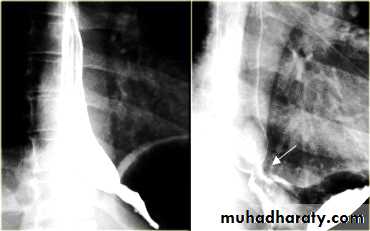

Esophageal Varieces

Dilatation of venous plexus in the wall of the esophagus due to increased pressure ( portal H.T.).

Important cause of Hematemesis .

Early changes seen in the mucosa (D.C.) loss of parallelism with thick and tortuous folds.

Later multiple small filling defects (fine cobble stone).

In advanced stage large filling defects ( coarse cobble stone ) .

7More advanced stage elongated and worm like filling defect .

The changes are seen at lower third and gastric fundus.